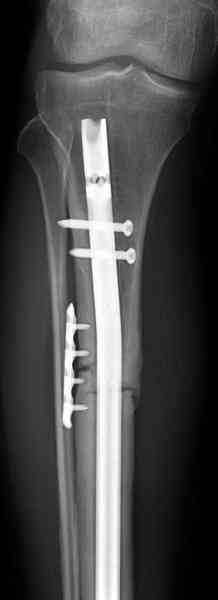

Недавно на нашей ежемесячной Morbidity&Mortality

conference мы разбирали похожий случай, ложный сустав большеберцовой кости после резекции опухоли.

К нашему онкологу-ортопеду обратился больной с жалобами на боли в голени, из рассказа - год назад была сделана биопсия большеберцовой кости, но название заболевания "не запомнил”.

Оперирован в военном госпитале с заменой сегмента

аллокостью большеберцовой кости и после демобилизации явился для постоянного наблюдения по месту жительства.

Наши имели проблему со сращением, пришлось им сделать динамизацию, дополнительную аутопластику.

Снимки представлены.